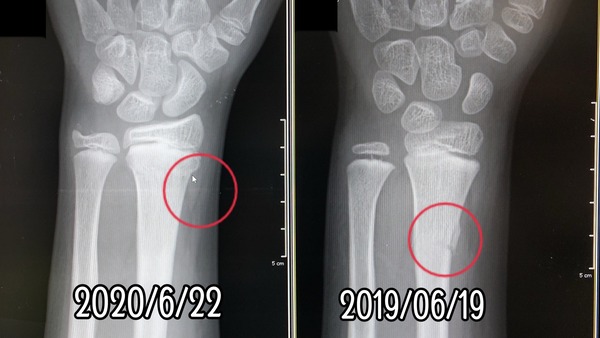

同じ骨の似たような部位を折ってます。

左の前腕〜手首付近の骨折。

やっぱり去年と同じような骨折で、

治療内容や経過もほぼ同じ感じらしい。

前年の骨折と全く同じような骨折だったから、

で、実際、去年のより、

場所的に治りは早そうとの事。

特に後遺症になるような骨折ではありません。